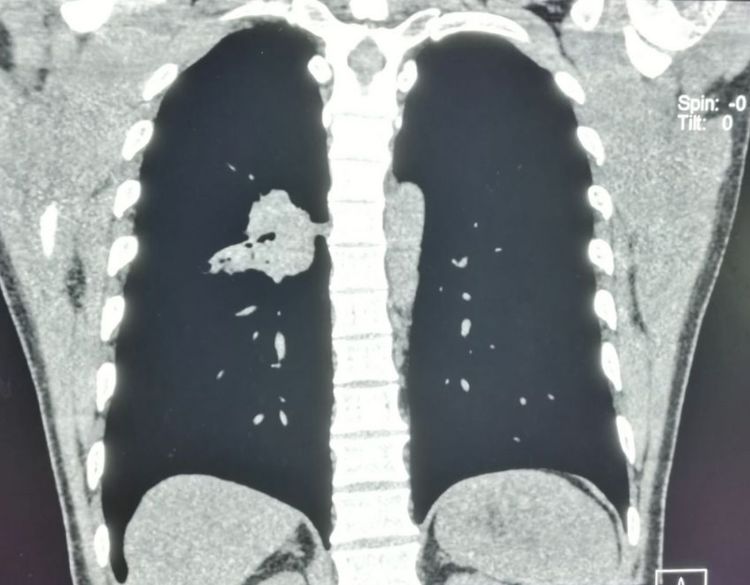

下图是一位有点消瘦的老爷子,吸烟接近50年,咳嗽、痰中带血,胸部CT加支气管镜发现左侧肺鳞癌,肿瘤内部已经形成了空洞:

在前面的“豪大夫讲肺结节”系列中,我们提到过伴有空洞形成的肺鳞癌预后差,中位生存期平均只有17个月,而没有空洞者,可以达到92个月,差异巨大。

这是因为空洞型肺癌生长更迅速,病理上更容易发生坏死;更容易侵犯血管、淋巴管和胸膜。

在周围型肺癌中,肺鳞癌的空洞发生率大约是17%,腺癌是7%。